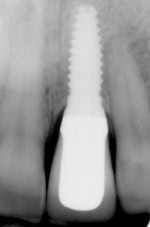

• There are about three parts that make up an implant restored tooth. The implant, which is surgically placed into the jaw and acts as the root. The post, which screws into the implant to connect the implant to the crown. Then finally the crown, which is cemented or screwed onto the post.

• To have an implant placed and completed start to finish can take between 3-6 months. However with each person the timeline may vary. Time can be added to this treatment if the area needs to have bone grafting. Bone grafting helps regenerate missing bone in areas where there is not enough space for an implant. This can add about 3-6 months to your overall procedure timeline as the grafting is normally done before the implant surgery.

Knowing the parts necessary in placing and restoring a dental implant can give us an idea as to why there is such a difference in price.  At Frangella Dental the fee for surgical placement and restoration of a dental implant is priced as a service and NOT as a commodity. The parts that make up the implant are generally a universal cost to the practitioner with the exception of the type of crown used and if you need a custom post rather than a stock post. These fees can be dependent upon which dental lab is used as well. That being said, a dental implant is just a tool or material that a practitioner uses for this type of procedure.  And, all practitioners are not created equal. So when asking yourself is this deal too good to be true, ask your practitioner these  questions and you’ll know. 1. Have you had any training in implantology? And if so how long was your program? 2. What is your success rate? is it above 90% 3. How long have you been placing implants? 4. And lastly, Does this fee include treatment planning, possible bone grafting as well as the restoration of the implant? These few questions should help you make an educated decision about your treatment and most likely allow you to feel more confident with your practitioner. It never hurts to be an educated consumer and remember,  you should always feel comfortable discussing your treatment with your dentist.  ]]>